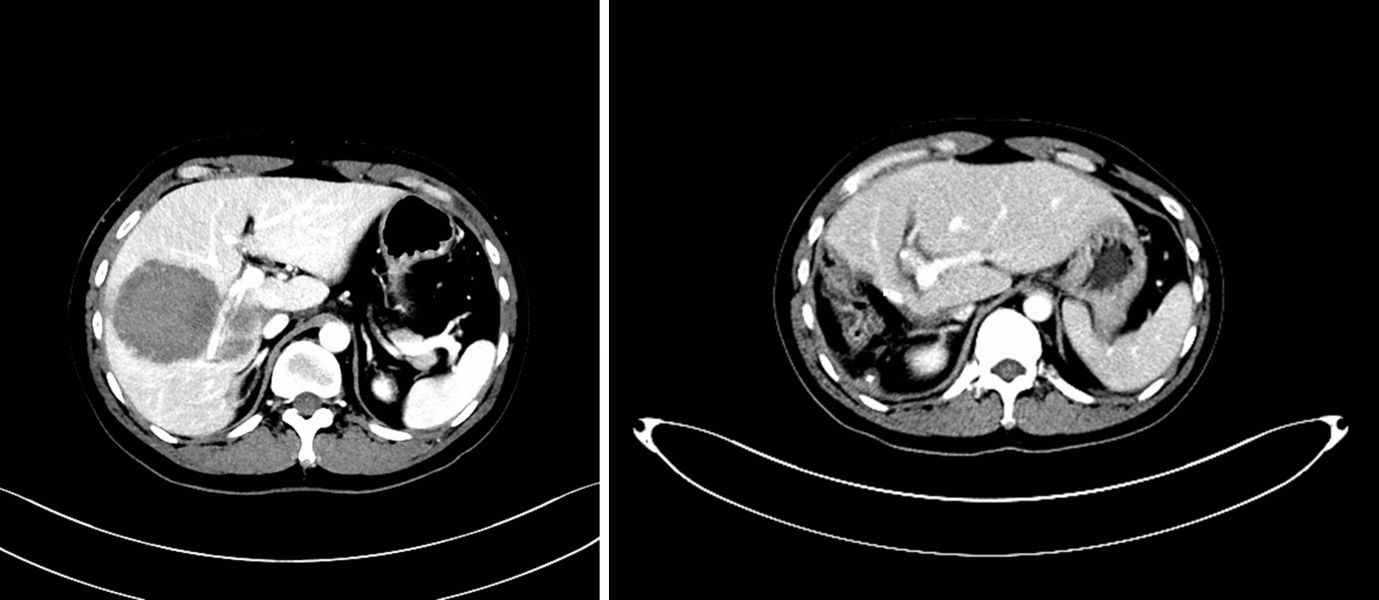

术前CT与术后CT(保留肝中静脉)对比图